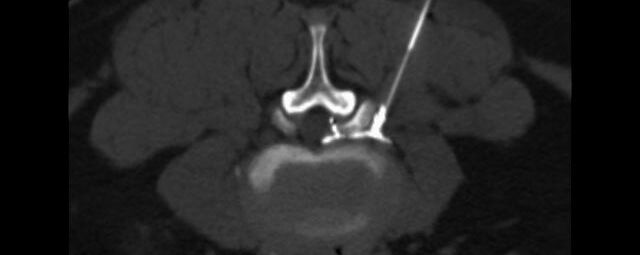

Wirbelsäule

• Darstellung von Frakturen, Tumoren und Bandscheibenveränderungen

Interventionelle Eingriffe

• z. B. Punktionen zur Gewebsentnahme

Schmerztherapie

Der Multislice-Scanner ermöglicht eine dem aktuellen Stand der Technik entsprechende, leitliniengerechte diagnostische Untersuchung sämtlicher Körperregionen. Darüber hinaus gestattet der neue Computertomograph auch eine für Arzt und Patient bequeme Durchführung CT-gestützter Interventionen wie z.B. Schmerztherapien der Wirbelsäule.